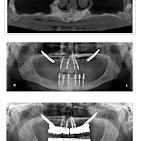

• Dental Implants & Full Mouth Implants: Permanent solutions for missing teeth, including advanced Zygomatic Implants for patients with bone loss.